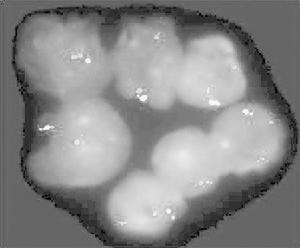

病理變化:主要為毛細胞的浸潤,浸潤脾臟所致的進行性脾腫大和脾功能亢進,組織學檢查顯示脾臟正常結構完全破壞,脾小體萎縮,毛細胞在脾穿刺液塗片中占80%~100%。浸潤骨髓造成血功能抑制,導致任1項血細胞減少,以血小板減少及中性粒細胞減少最常見,多數病人尚有單核細胞減少。